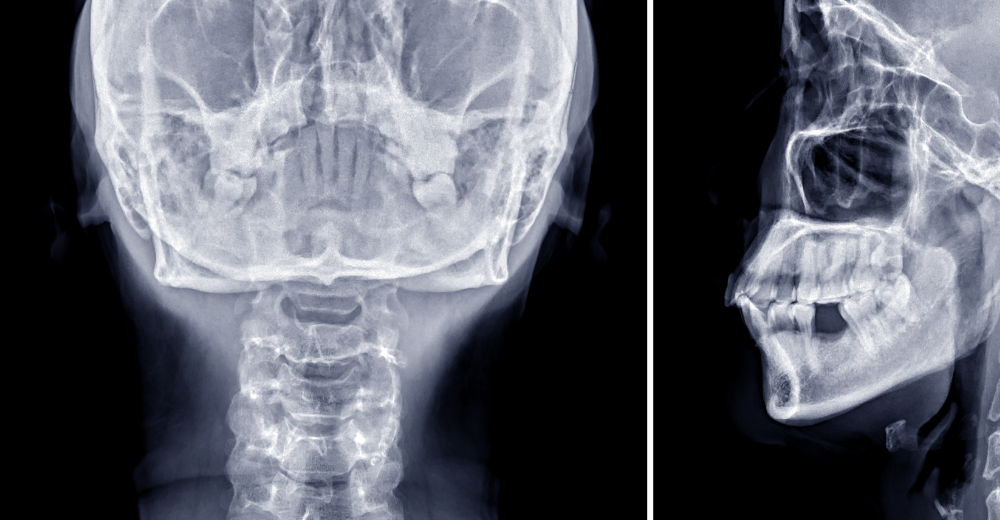

L’RX Orbite è un esame radiologico non invasivo che permette di acquisire immagini dettagliate delle orbite oculari. Il paziente viene posizionato davanti a una macchina a raggi X e, grazie a questa tecnologia, si ottiene una visualizzazione chiara delle strutture interne. Le immagini mostrano non solo le ossa, ma anche i muscoli oculari e i tessuti molli circostanti, consentendo ai medici del Poliambulatorio S-Medical Group di Sora di valutare con precisione ogni potenziale anomalia.

Durante l’esame di RX Orbite, il paziente viene esposto a una dose molto bassa di radiazioni ionizzanti. Le radiazioni attraversano i tessuti e le ossa dell’orbita, generando un’immagine radiografica precisa che permette di distinguere le diverse strutture. I tessuti più densi, come le ossa, appaiono più chiari, mentre i tessuti molli risultano più scuri. Questo contrasto consente ai medici di individuare eventuali anomalie con grande accuratezza.

L’RX Orbite permette di osservare le ossa che costituiscono le pareti dell’orbita (mediale, laterale, superiore e inferiore), la posizione del bulbo oculare, i muscoli oculari, i nervi ottici e le strutture vascolari. Queste informazioni dettagliate sono fondamentali per identificare fratture, alterazioni strutturali o anomalie nella posizione degli occhi.